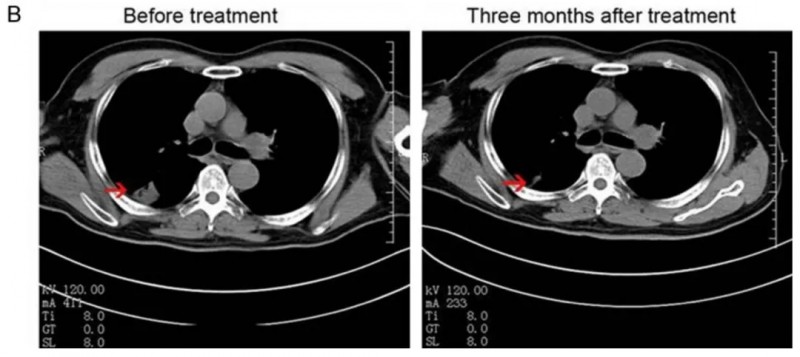

值得一提的是,其中一位53岁IVA期男性患者的治疗效果尤为突出:经NK细胞联合西妥昔单抗治疗后,肿瘤显著缩小。CT扫描显示,其右肺肿瘤从治疗前的3.5×3.5cm,缩小至治疗后的1.7×1.3cm(详见下图)。

▲图源“Am J Cancer Res”,版权归原作者所有,如无意中侵犯了知识产权,请联系我们删除